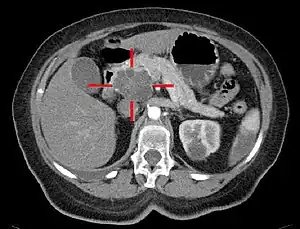

As técnicas de imagiologia médica, como a tomografia computadorizada ou ecoendoscopia, são usadas para confirmar o diagnóstico e ajudar a decidir se o tumor pode ou não ser removido com cirurgia.[11] É também possível recorrer a imagem por ressonância magnética ou tomografia por emissão de positrões,[2] e nalguns casos a colangiopancreatografia por ressonância magnética.[27] A ecografia abdominal é menos sensível e pode não detetar pequenos tumores, embora possa identificar cancros que se tenham propagado para o fígado e a acumulação de fluido na cavidade peritoneal (ascite).[11] Pode ser usado numa avaliação rápida, não invasiva e barata antes de outras técnicas.[40] Nos casos em que não há certeza sobre o diagnóstico, pode ser realizada uma biópsia através de punção aspirativa por agulha fina, geralmente orientada por ecoendoscopia. No entanto, geralmente não é necessário um diagnóstico histológico para decidir a remoção do tumor através de cirurgia.[11]